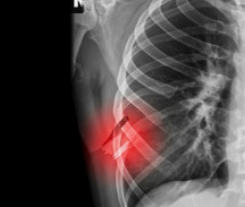

- 붓기와 멍: 외상에 의한 경우 부종과 멍자국이 생기기도 함

갈비뼈 금간 진단 방법

갈비뼈 금간 여부는 병원에서 다음과 같은 검사를 통해 진단합니다:

- 흉부 X-ray 촬영